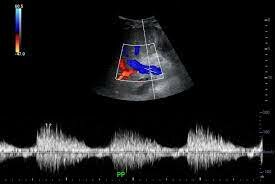

Surge la ecografía Doppler a color con imagen bidimensional, este método permitió visualizar en tiempo real el flujo sanguíneo.